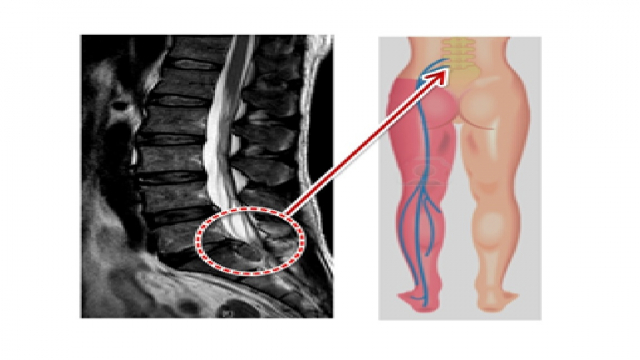

허리디스크는 척추 뼈 사이에 위치한 연골과 같은 구조물인 디스크가 손상되어 발생하는 상태입니다. 보통 나이가 들어감에 따라 이러한 문제가 발생하는 경향이 있지만, 무리한 운동이나 잘못된 자세로 인해 젊은 사람들도 겪을 수 있습니다. 허리디스크는 척추 신경을 압박하여 여러 가지 증상을 유발할 수 있습니다.

허리디스크의 증상은 개인에 따라 다를 수 있지만, 일반적으로 다음과 같은 증상이 나타날 수 있습니다. 첫째, 허리 통증입니다. 허리에 지속적인 통증이 있거나, 특정 자세를 취했을 때 더욱 심해질 수 있습니다. 이 통증은 엉덩이, 허벅지, 종아리 부위로 방사될 수 있습니다.

둘째, 다리 저림이나 쑤시는 느낌이 있을 수 있습니다. 하반신에 저림이나 무거운 느낌이 발생하면, 이는 허리디스크로 인한 신경 압박의 결과일 수 있습니다. 셋째, 마비 증상이 발생할 수 있습니다. 허리디스크가 신경을 압박하여 다리나 발의 특정 부위가 감각이 없어지거나 마비되는 경우가 있습니다.